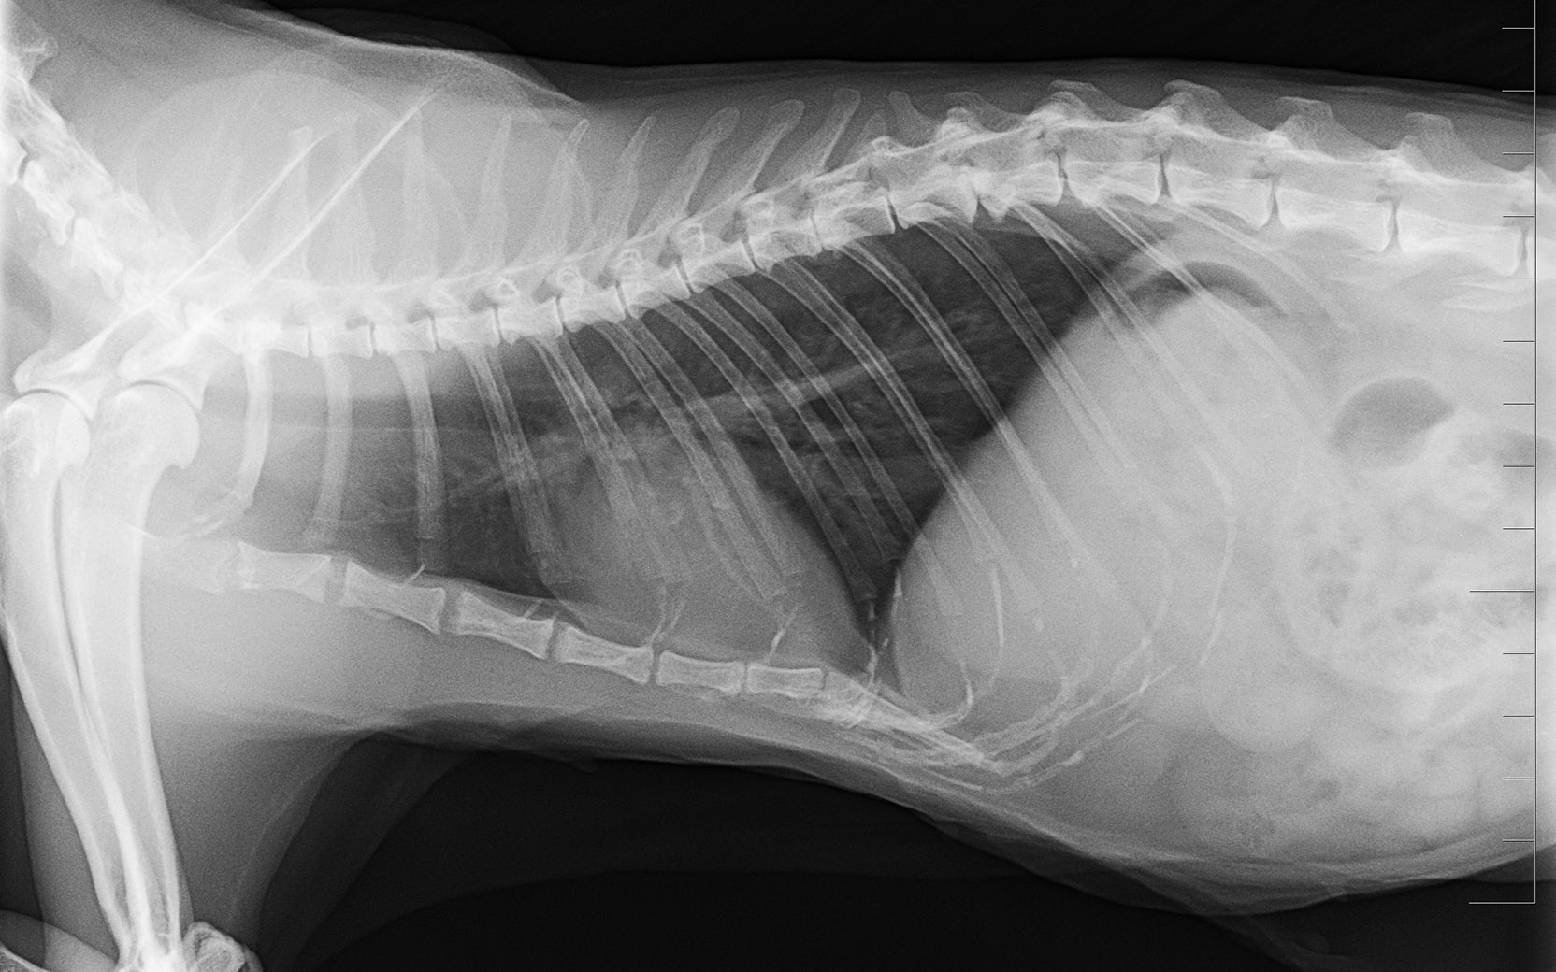

Mit Hilfe einer Blutuntersuchung können herzspezifische Werte ermittelt werden, deren Höhe Auskunft über die Wahrscheinlichkeit einer HCM geben. Durch eine Röntgenuntersuchung können Größe und Form von Herz und Lunge bestimmt und eventuelle Flüssigkeitsansammlungen in der Lunge, das sogenannte Lungenödem und im Brustraum, ein sogenannter Brusthöhlenerguss, festgestellt werden.